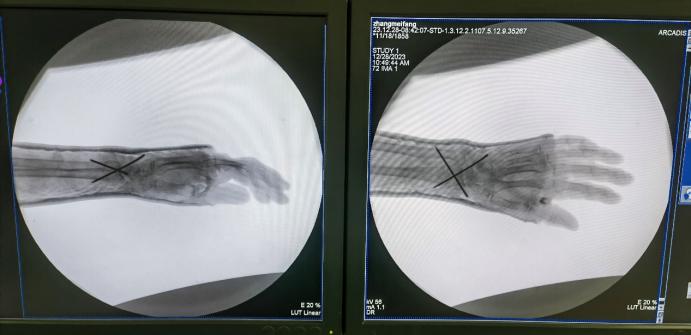

此次手术为女性患者,89岁,入院前1日因跌倒导致右股骨粗隆间骨折合并右桡骨远端粉碎性骨折,症状为右下肢及右腕关节肿胀、畸形伴活动受限,严重影响日常生活,保守治疗卧床时间长且效果不佳。患者既往身体较差,患有冠状动脉粥样硬化性心脏病、心律失常(房性早搏合并室性早搏)、高血压(2级,极高危)、脑梗死后遗症,患者前往多家医院诊治,均因患者的全身情况对于手术是一个巨大挑战而被婉拒。

患者桡骨远端骨折